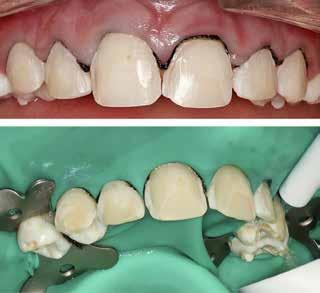

Fig. 1. 40-årig sund og rask mand møder bekymret for sine slidte tænder. Klinisk ses frakturer og substanstab langs incisalkanterne på overkæbetænderne.

Fig. 1. A 40-year-old healthy man is concerned for his worn teeth. Clinically, fractures and loss of tooth substance are observed at the incisal edge of the upper front teeth.

Okklusalt billede af A) over- og B) underkæbe

2. Klinisk ses tydelig slitage ind i dentinen på samtlige tænder fra 6’er til 6’er i begge kæber.

Fig. 2. Clinically, extensive wear into the dentin of all teeth in both jaws is observed.

Klinisk undersøgelse viste et tandsæt med enkelte restaureringer, men med slitagedefekter okklusalt/incisalt på samtlige tænder fra 6’er til 6’er i over- og underkæbe (Fig. 2). Defekterne strakte sig tydeligt ind i dentinen. Baseret på anamnesen og de kliniske fund blev erosion set som hovedårsagen til tandsliddet, mens attrition formodedes at være en medvirkende faktor.